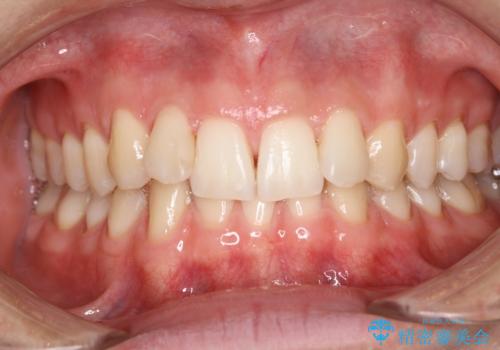

エアフロー60分コースを行いました。

着色の除去後に、ご自身の本来の歯の色をご確認していただいたところ、この状態で満足とのことでした。

クリーニングは、汚れの除去を行いますので歯を白くする処置ではありません。ご自身本来の歯の色にすることが可能です。